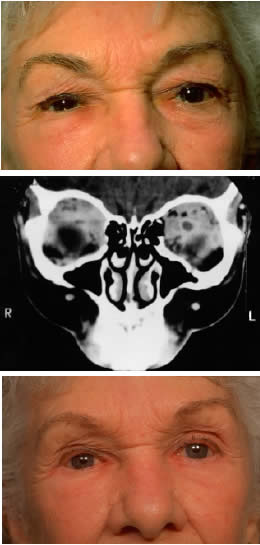

Fig. 12. An 81-year-old white woman had been aware of a pigmented lesion in the left caruncular region for 18 months. It had gradually increased in size and had bled on several occasions. In addition, she was aware of a lump on the left side of her neck for 6 weeks. On examination, a large, nodular, pigmented medial conjunctival lesion associated with thickening and induration of the tarsal conjunctiva was noted, as was a nodular satellite lesion in the temporal aspect of the inferior fornix due to local lymphatic spread (A). There was lateral displacement of the globe and some limitation of abduction. Axial CT scan demonstrates the irregularly shaped mass in the anterior orbit involving the insertion of the medial rectus muscle (B). The patient refused exenteration and underwent local resection, cryotherapy, mucous membrane graft, and radical neck dissection. Of 31 neck nodes removed, 2 were positive for metastatic disease. Nodular recurrence developed in her left jaw, and the patient died 1 year after presentation without evidence of local ocular recurrence. (Rootman J, Ragaz J, Cline R, Lapointe JS: Metastatic and secondary tumors of the orbit. In Rootman JR (ed): Diseases of the Orbit: A Multidisciplinary Approach, pp 405–427. Philadelphia, JB Lippincott, 1988.)